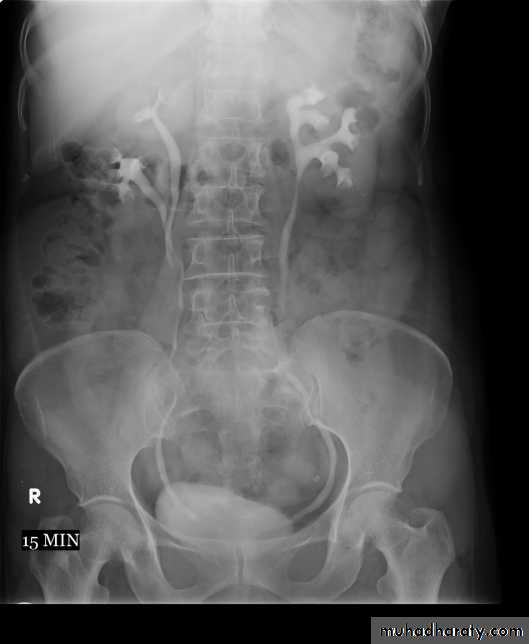

2. Pyelogram Phase (1- 5) minutes after injection of contrast) .3. After 10 minutes with compression, to get better distention of the pelvis and calyces.

4. Full length film after release of compression .